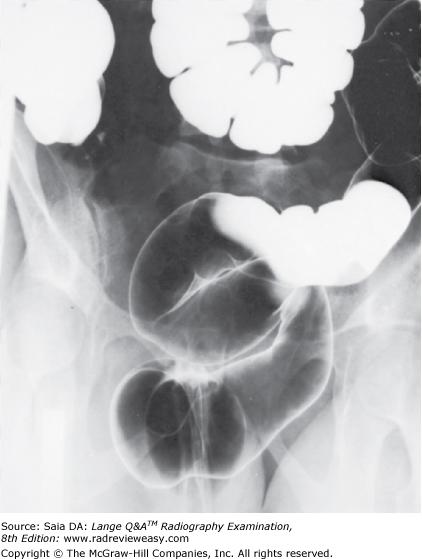

The radiograph pictured in Figure A may be used to evaluate

1.polypoid lesions.

2.the lateral wall of the descending colon.

3.the posterior wall of the rectum.

A 1 only

B 1 and 2 only

C 2 and 3 only

D 1, 2, and 3

-The pictured radiograph was made in the right lateral decubitus position. It is part of a series of radiographs made during an air-contrast (double-contrast) BE examination. A double-contrast examination of the large bowel is performed to see through the bowel to its posterior wall and to visualize any intraluminal (eg, polypoid) lesions or masses. Various body positions are used to redistribute the barium and air. To demonstrate the medial and lateral walls of the bowel, decubitus positions are performed. The radiograph presents a right lateral decubitus position, because the barium has gravitated to the right side (the side of the hepatic flexure). The air rises and delineates the medial side of the ascending colon and the lateral side of the descending colon. The posterior wall of the rectum could be visualized using the ventral decubitus position and a horizontal beam lateral of the rectum.